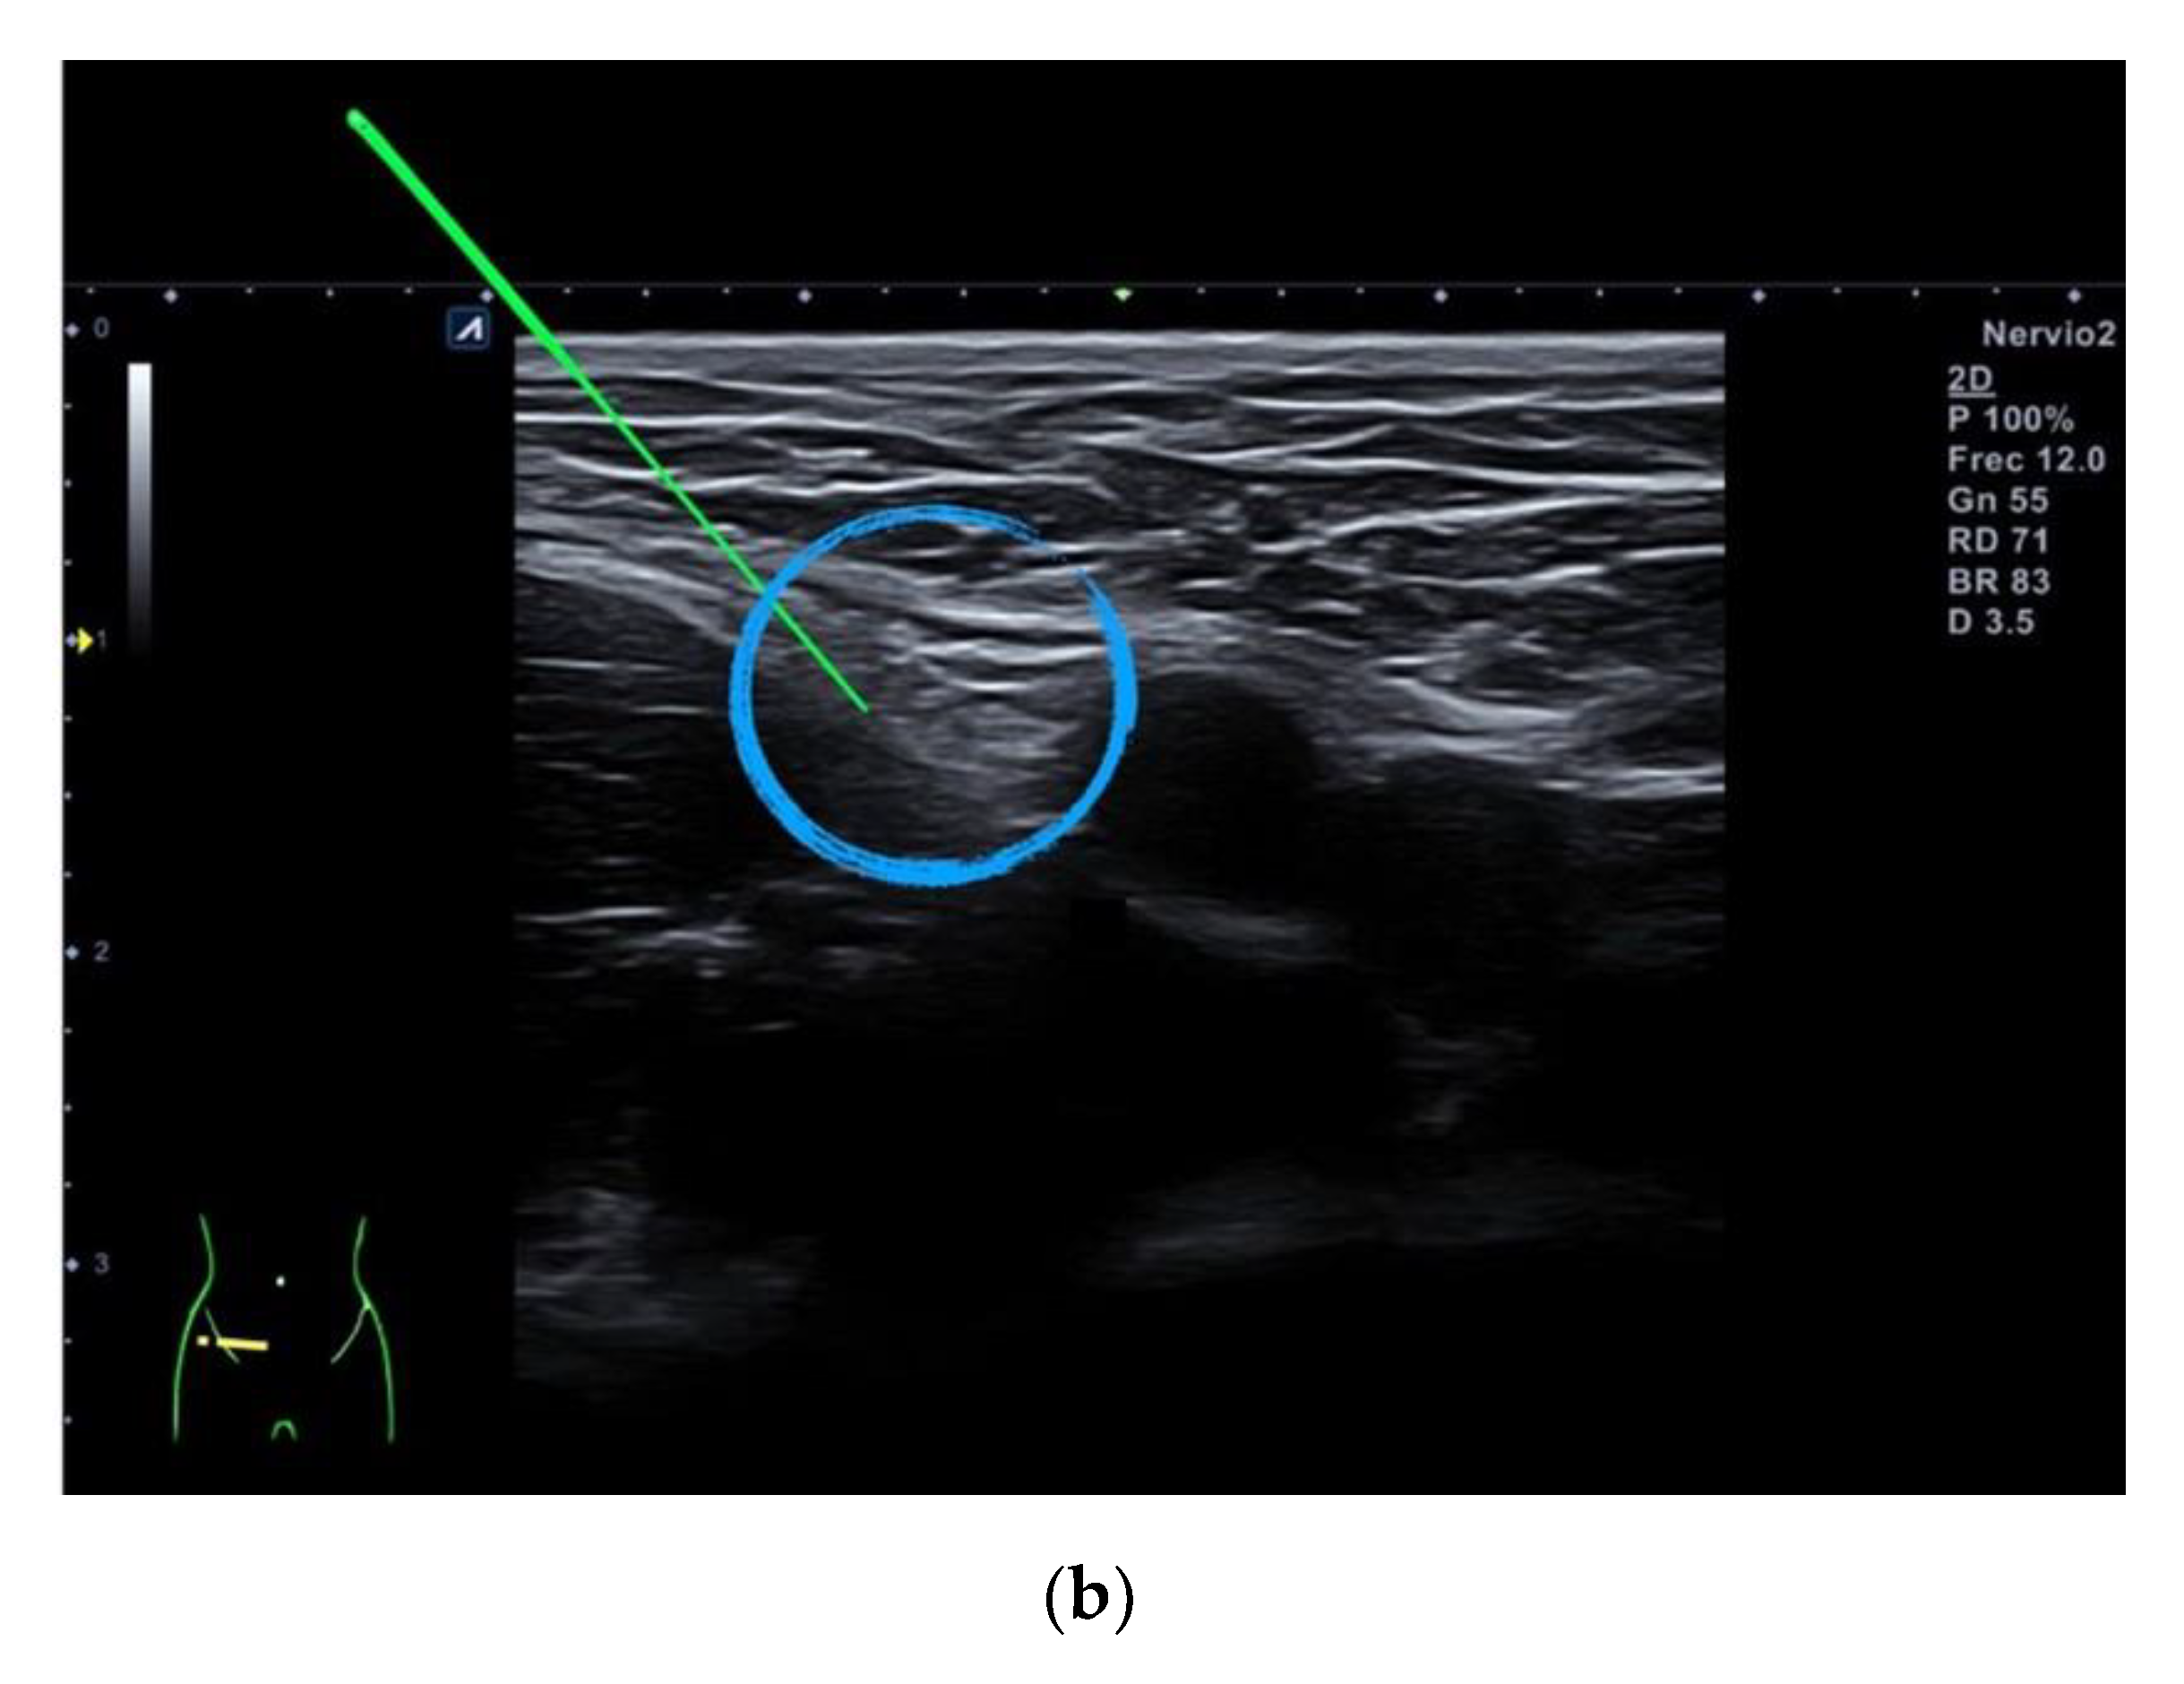

2.4. Percutaneous Electrical Nerve Stimulation